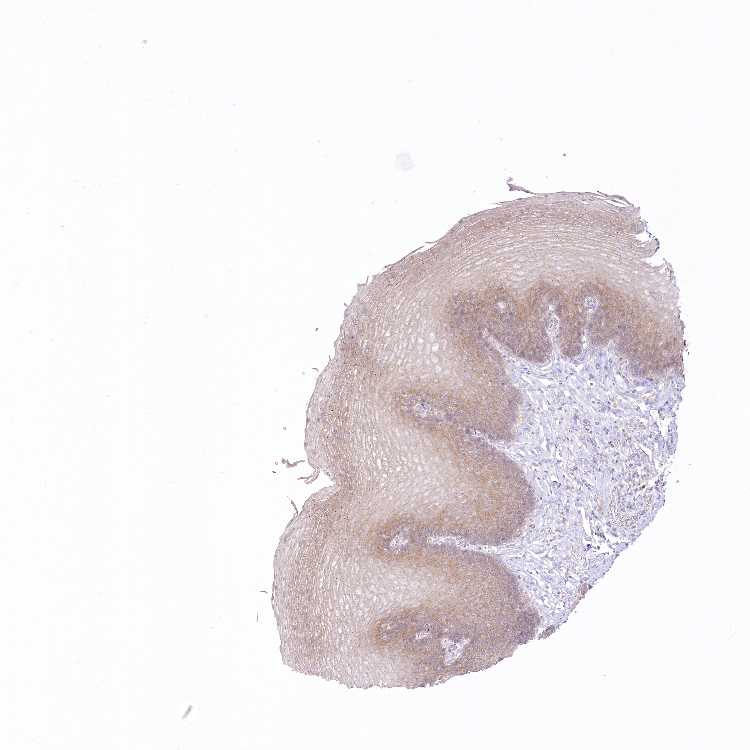

ESOPHAGUS - Antibody stainingi

Antibody staining in the annotated cell types in the current human tissue is reported as not detected, low, medium, or high, based on conventional immunohistochemistry profiling in selected tissues. This score is based on the combination of the staining intensity and fraction of stained cells.

Each image is clickable and will lead to virtual microscopy that enables deeper exploration of all samples and also displays staining intensity scores, fraction scores and subcellular localization as well as patient and tissue information for each sample.

Antibody HPA030911Antibody HPA030912

Squamous epithelial cells MediumNot detected